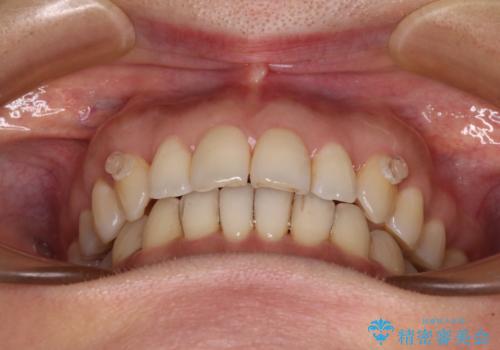

矯正治療の後戻り インビザライン・ライトによる矯正治療

- 矯正治療の後戻りを気にして来院された患者様です。

後戻りは軽微であったので、インビザライン・ライトにより矯正治療を行うこととしました。

インビザライン・ライトは提供されるマウスピースの数に制限があり、通常のタイプよりもマウスピース提供期間が短くなっている一方、安価に治療を行うことができるプランです。

治療のゴールも変更できないため、軽微な歯列不正や、後戻り改善などに適しています。